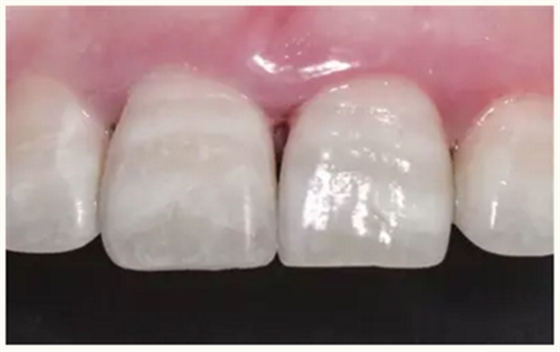

牙体树脂美学修复适用于对牙体修复效果有美学要求的前牙或者后牙。对于患者而言,前牙修复效果更为直观。因此,临床上对于前牙美学修复的需求更为迫切,常见的修复类型为及切角的前牙牙体缺损。治疗的过程一般为①比色、②缺损牙体的树脂预修复(直接修复)或者取模翻制石膏模型的基础上制作蜡型恢复缺损牙体(间接修复),③硅橡胶制作舌侧导板,④上橡皮障,牙体预备(洞缘斜面),⑤酸蚀、粘结,⑥树脂分层充填,⑦修形、抛光,⑧完成。

▲术后即刻(唇侧)

▲术后即刻(舌侧)